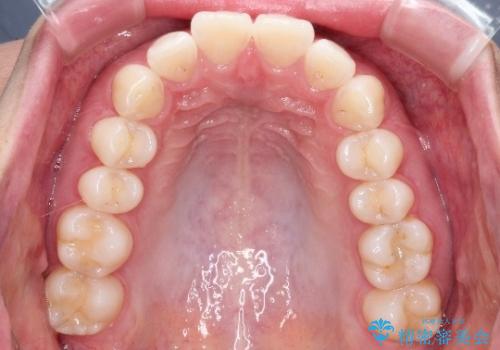

【前歯のガタガタが気になる】インビザライン症例

- 前歯の歯並びの改善を希望され来院された患者様です。

初診時の歯並びの状態としては、下顎前歯に及ぶの中等度のがたつき(叢生)があり、前歯が深く噛みこんでいる状態でした。

抜歯は行わず歯列弓の拡大やディスキング(歯と歯の間の隙間を作る処置)を行い叢生を改善しました。

矯正装置としてはマウスピースを使用しています。